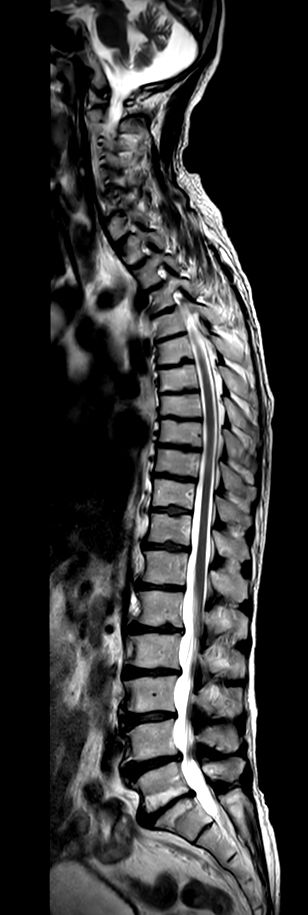

Whole Spine with scoliosis (2 stations)

Sagittal T1w TSE (2 stations)Compressed SENSE

Sagittal T2w TSE (2 stations)Compressed SENSE

Sagittal STIR TSE (2 stations)Compressed SENSE